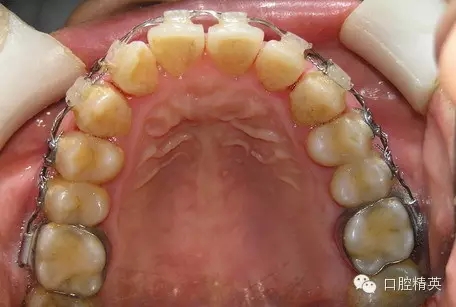

鄰面去釉臨床操作步驟組圖

圖1

1、在操作時要注意保護牙齦組織,鄰牙間隙齦乳頭上方插入牙科探針,在高速渦輪機金剛砂細錐形車針的精細切割下,可以很安全地給牙齒按矯治設(shè)計要求進行去釉操作(圖1~圖5)。注意握持手機的手要有穩(wěn)定的支點。

2、一般每個牙鄰面僅磨去0.25~0.30毫米的牙釉質(zhì),注意上下去釉厚度要均勻,應恢復牙冠應有的解剖外形;為了便于去釉操作,應在牙列排齊后進行。

提示:這里博客文章列舉的鄰面去釉步驟不是一個病例的照片,是選用幾個病例不同去釉階段的照片組合而成。其中有裝配金屬托槽矯治器的,也有陶瓷托槽的,主要是給正畸專業(yè)網(wǎng)友朋友們介紹其臨床操作步驟要點。是一個階段性治療狀況,不是一個最終治療結(jié)果。好的經(jīng)驗給大家展示,需要注意之處也暴露給大家,以便引起大家關(guān)注。圖12、圖13病例是5年前我們最初去釉治療的狀況,牙冠外形和鄰接點的問題,當時我們是關(guān)閉間隙后采取二期修形處理的。